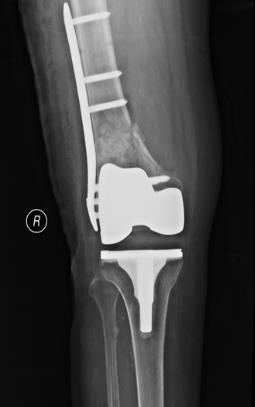

(六)膝关节置换术后假体周围骨折内固定术

(五)胫骨平台骨折内固定术

(七)膝骨关节炎的中医中药特色治疗